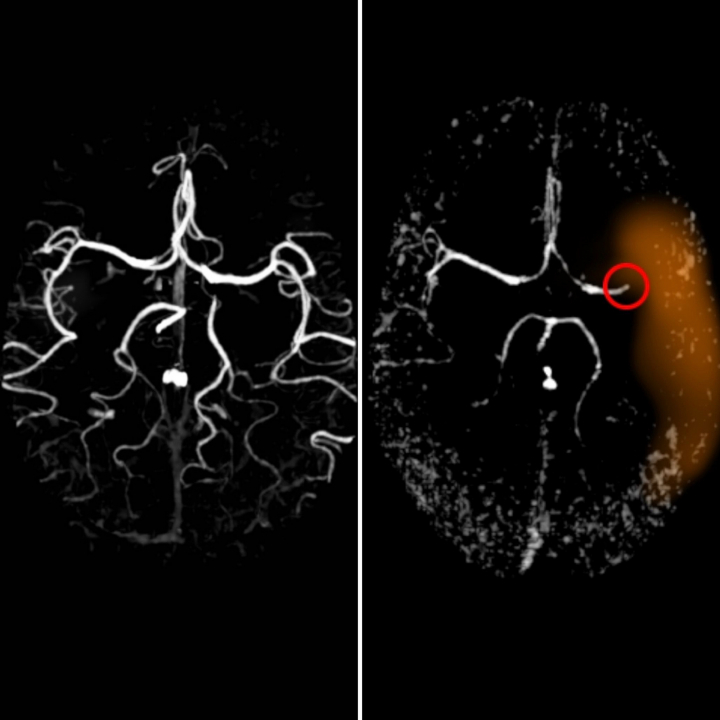

Para los ictus isquémicos podemos aplicar dos tratamientos diferentes: un fármaco por vena que intenta disolver el coágulo formado, pero que solo puede funcionar hasta las 4,5 horas desde que empiezan los síntomas. Y, la otra posibilidad, es la cirugía endovascular, un tratamiento que ha avanzado mucho en los últimos años que consiste en sacar el coágulo mediante catéteres, ya sea aspirándolo o cogiéndolo con una especie de pinzas. En este caso, el tiempo se amplía hasta las 24 horas desde la aparición de los síntomas, dependiendo de cada paciente.